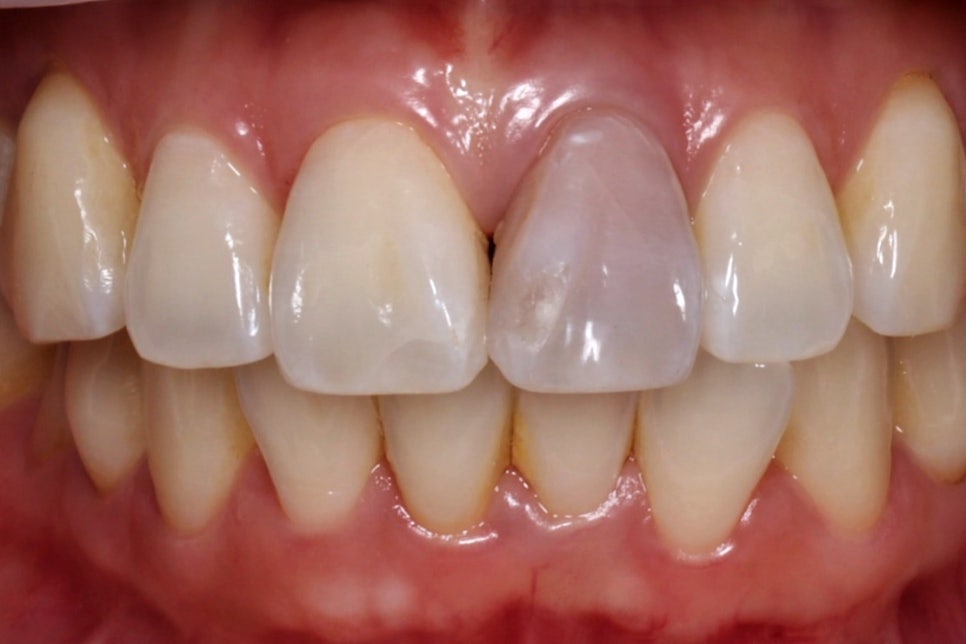

완료 후

한 2주 정도 기다리면 이렇게 건강한 자연치와 같은 모습으로 바뀌게 된답니다^^

그래서 저는 실활치 미백을 치아를 깎지 않고 색을 회복하는 과정이라고 설명드리고 있어요.

그래서 특히 젊은 환자분들의 경우에는 실활치 미백 → 레진 홀 메우기 이렇게만 하셔도 크라운 없이 하얀 치아를 얻을 수 있습니다.

크라운 없이 치료 완료

저는 치아는 한 번 삭제하면 다시 되돌릴 수 없기 때문에 살릴 수 있을 때 살려야 한다는 생각으로 매 진료에 임하고 있어요.

오늘 소개해 드린 실활치 미백은 치아의 본래 구조를 최대한 보존하면서 안쪽에서부터 맑은 빛을 되찾아주는 가장 '보존적인' 치료죠.